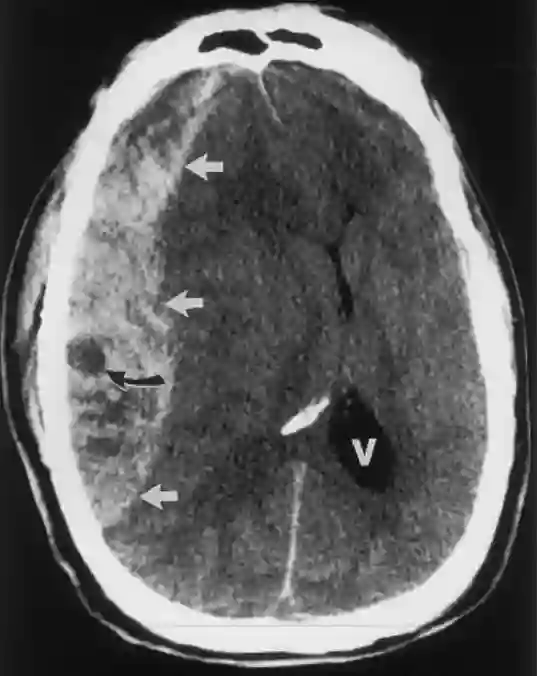

Swirl Sign CT

Axiale CT Bildgebung des Schädels einer hyperakuten Blutung (weiße Pfeile) mit Swirl Sign (schwarzer Pfeil).